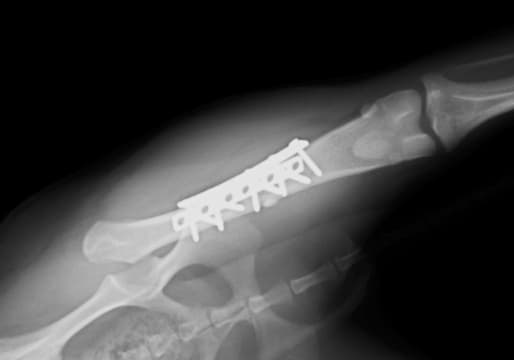

脛骨高平部水平化骨切り術(TPLO)は、脛骨を切ってプレートで固定することにより、脛骨の頭側への移動を防ぎ、膝を安定化させる手術です。

8kgを超えるワンちゃんには、この術式で行うことが多いです。